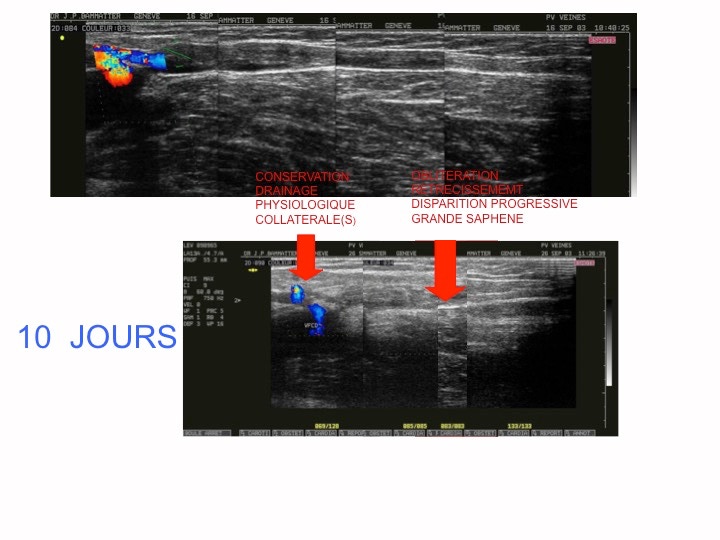

L’axe traité à chaud est laissé en place contrairement au stripping .

Sous l’effet de la radiofréquence ou du laser , il se rétracte  , s’oblitère et se résorbe progressivement .

A 10 jours , le processus est déjà visible . A 3 mois , il persiste un cordon fibreux qui va disparaitre en 1 an environ .